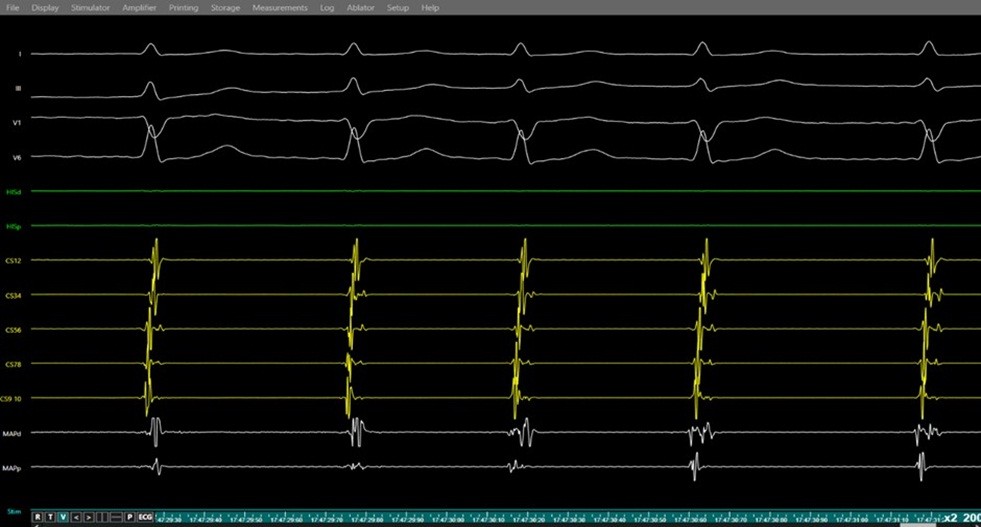

Figure 9. Junctional rhythm during slow pathway ablation

Simultaneous surface ECG (leads I, II, V1, V6) and intracardiac electrograms (coronary sinus, and ablation catheter) demonstrating junctional rhythm occurring during radiofrequency energy delivery at the slow pathway region a marker of effective slow pathway modification during AVNRT ablation.

AVNRT - atrioventricular nodal re-entrant tachycardia, ECG – electrocardiogram